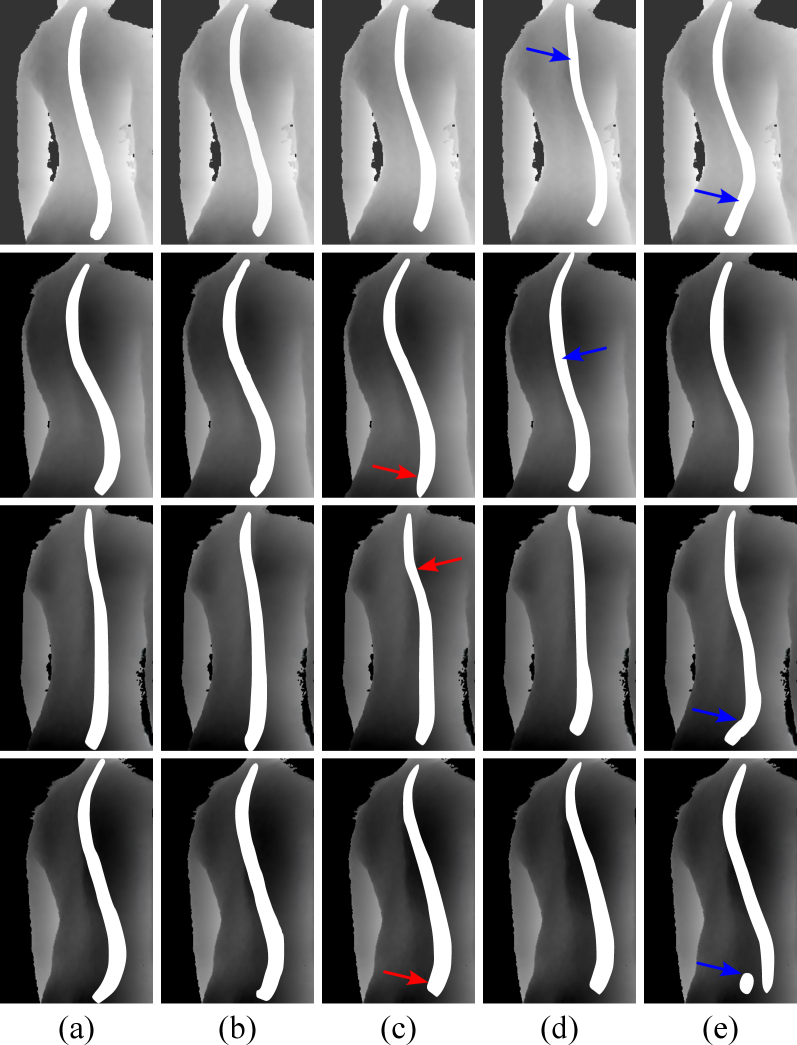

Refer to caption

Figure 4: Visual comparison of spine curve map generation. The white mask denote the spine region. The five columns are: (a) spine curve GT, (b) SME stage with SDN, (c) SME stage without SDN, (d) Pix2PixGAN, (e) Pix2PixHDGAN, respectively.

We evaluate the performance of our proposed SME module against two advanced GAN-based models, namely, Pix2PixGAN [36] and Pix2PixHDGAN [37].To ensure fair comparison, all models were trained under identical conditions, including consistent input/output formats, discriminator architectures, and loss items. Table 1 reports the quantitative results for lateral spine curve generation. Our SME module, particularly when integrated with the SDN, achieves the best overall performance.

Notably, even without SDN, our generator based on the proposed ARFFC blocks significantly outperforms the traditional ResNet-based architectures used in Pix2PixGAN and Pix2PixHDGAN, highlighting the effectiveness of the ARFFC design. Fig. 4 presents the visual comparison of generated spine curves. The ARFFC-based generator better preserves the global curvature trend, as illustrated by the blue arrows (\mathbf{\rightarrow}) in Fig. 4, which highlight areas where compared models deviate from the ground truth. Furthermore, the red arrows (\mathbf{\rightarrow}) in Fig. 4 mark areas with insufficient detail reconstruction. The inclusion of SDN further enhances local curve accuracy, demonstrating its utility in modeling fine-grained geometric deformations. The SME module demonstrates high efficiency, requiring on average 0.05 seconds per image and approximately 2.5 GB of GPU memory. Despite SME ensuring alignment with RGBD inputs, curve estimation errors (under- or overestimation) may still propagate into the synthesized radiographs and affect anatomical fidelity.